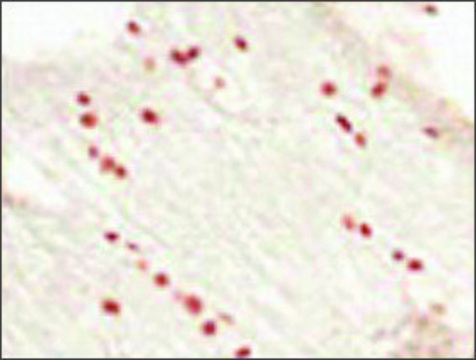

Rabbit polyclonal anti-OLIG2 antibody is used to tag oligodendrocyte lineage transcription factor 2 for detection and quantitation by immunocytochemical and immunohistochemical (IHC) techniques. It is used as a probe to determine the presence and roles of oligodendrocyte lineage transcription factor 2 in ventral neuroectodermal progenitor cell fate and as a diffuse glioma marker protein.

Oligodendrocyte lineage transcription factor 2 (OLIG2), a basic helix-loop-helix transcription factor, is an essential regulator of ventral neuroectodermal progenitor cell fate and is required for oligodendrocyte and motor neuron development. OLIG2 is a universal marker of diffuse gliomas including oligodendroglioma, astrocytoma, glioblastoma, and mixed glioma.